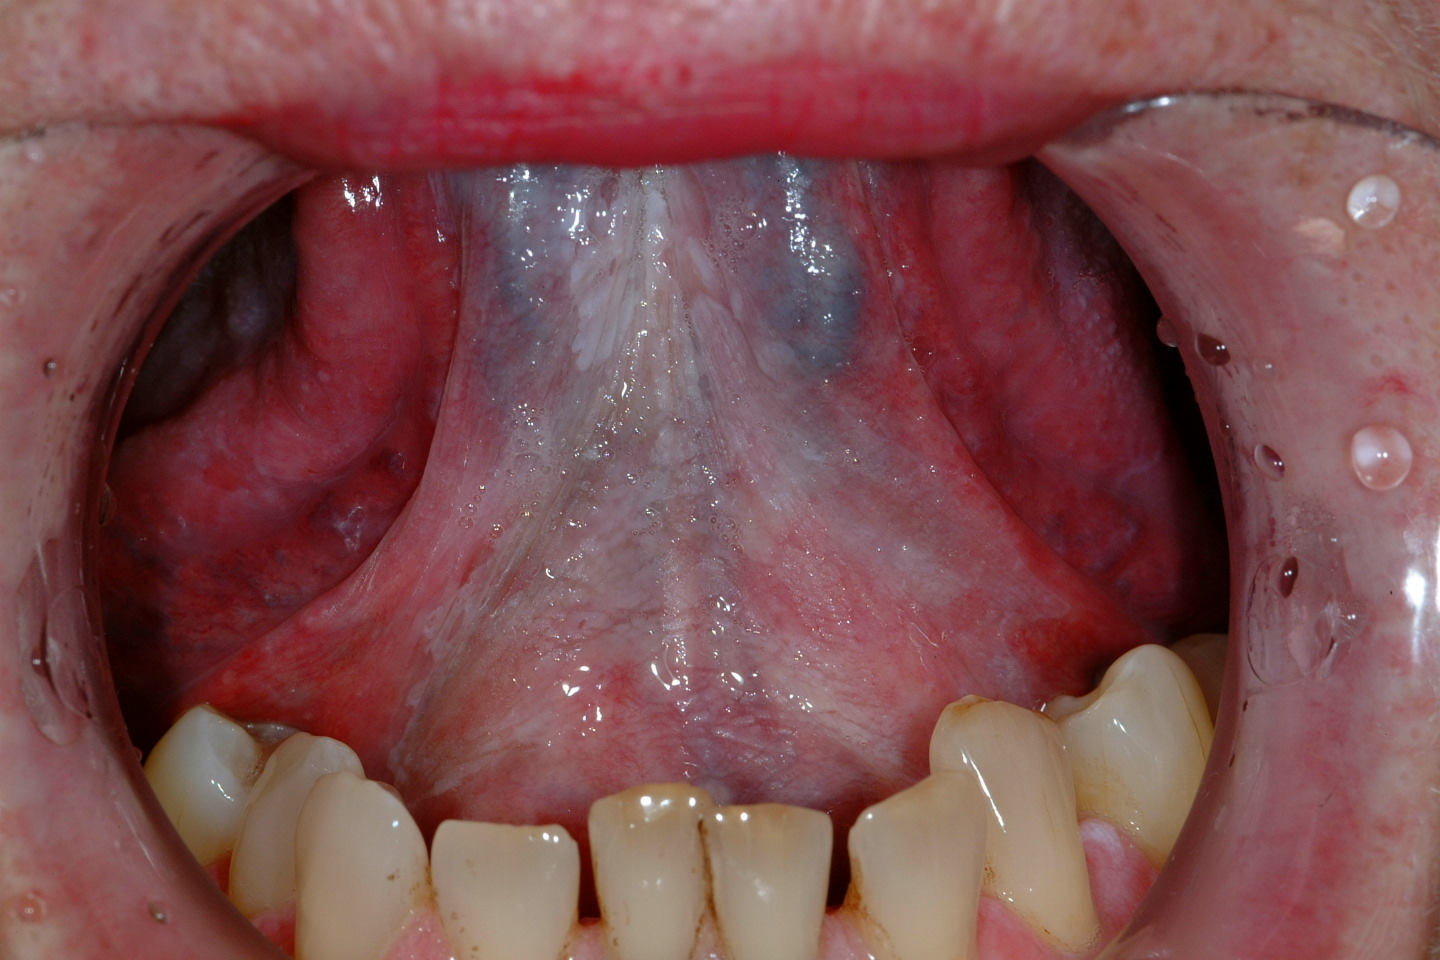

An oral leukoplakia (WHO definition) is a white patch or plaque that cannot be characterized, clinically or histopathologically, as any other disease. Erythroplakia can be similarly described but for bright red patches or plaques. Erythroleukoplakia (speckled leukoplakia) forms the third lesion commonly associated with risk of malignant transformation. This risk has been reported to be 2-6% for leukoplakia (varies with sites, e.g. highest in floor of mouth). 40-50% of erythroplakias have high grade dysplasia or carcinoma present. Speckled leukoplakia is of intermediate risk.

Figure 1: An example of leukoplakia, anterior floor of the mouth.